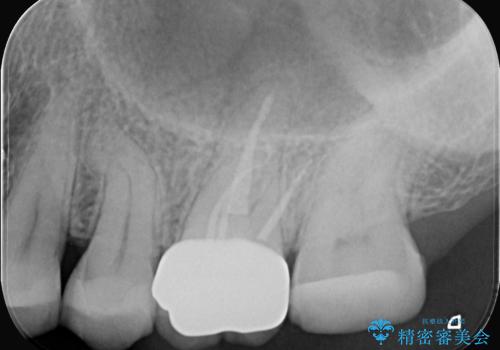

- 右上の歯の痛みを主訴にご来院されました。精密な診査の結果、虫歯が深く進行し、歯の神経(歯髄)にまで炎症が及んでいると診断。このままでは痛みが治まらず、歯を失うリスクもあるため、まず痛みの原因である感染した神経を取り除く根管治療を提案しました。根管治療によって歯の土台を整えた後、歯の破折を防ぎ長期的に機能させるため、**クラウン(被せ物)**を装着して修復する治療計画を立案しました。

治療はまず、感染源を徹底的に除去する根管治療から開始しました。治療の精度を高めるため、ラバーダムや顕微鏡などを使用し、根管内を丁寧に清掃・消毒。これにより、痛みの原因を根本から取り除きました。

根管治療が完了し、歯の内部が清潔で安定した状態になった後、歯を保護し、強い咬合力に耐えられるよう**クラウン(被せ物)**を装着しました。クラウンは、患者様の希望や咬み合わせの状態に応じて、機能性・審美性に優れた素材を選択し、精密に作製しました。